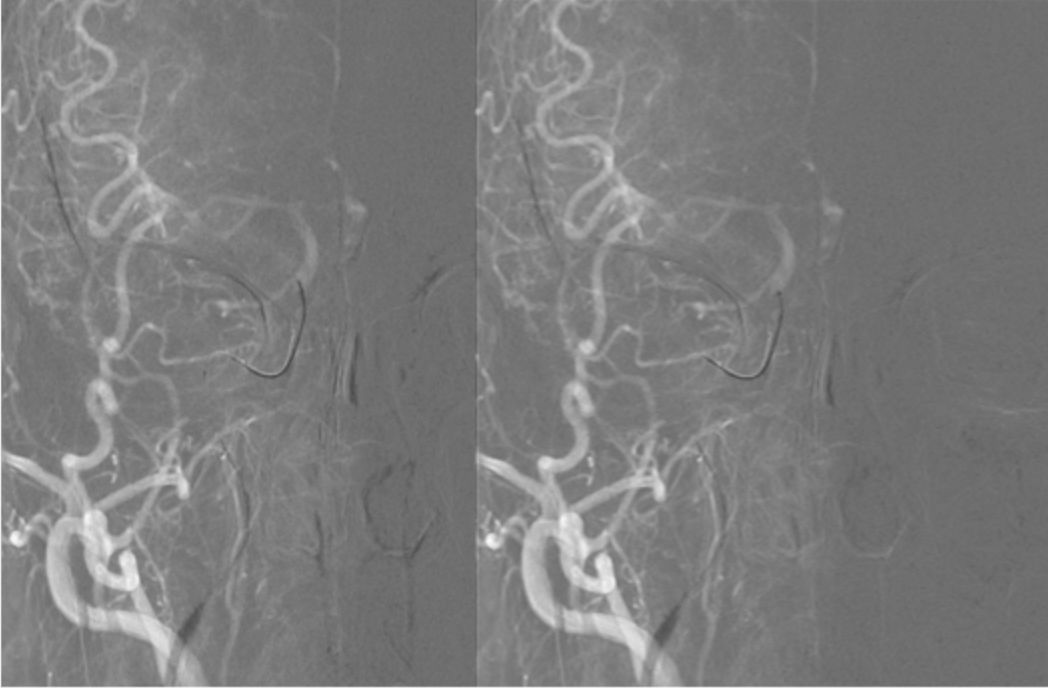

撤出PILOT 50微导丝,沿MOMA送入Synchro微导丝(0.014"x190 cm)+Headway 21微导管至右侧颈内动脉C1段,撤出微导管,将Synchro微导丝送入右侧大脑中动脉M1段,沿Synchro微导丝送入WALLSTENT支架(9 mmx50 mm)至C1段末端,定位准确后充盈MOMA球囊释放支架成功,抽瘪MOMA球囊,撤出支架输送装置。造影显示支架完全覆盖C1狭窄段(图9)。

图9

与血管壁贴合良好,无急性血栓形成。远端未放支架血管残余狭窄仍较重,沿Synchro微导丝送入Ultra-soft球囊(2.5 mmX20 mm)球囊,使用MOMA近端保护技术,依次由远到近对残余狭窄段进行扩张(图10),造影显示残余狭窄段较前改善。观察10 min,行右侧颈总动脉正侧位造影,显示右侧大脑中、前动脉及分支动脉显影良好,可见支架内血流通畅,无急性血栓形成(图11)。

图10

图11